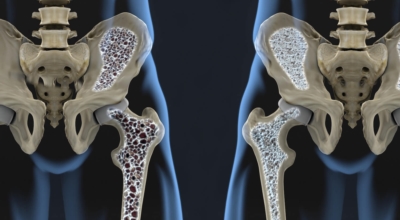

골다공증이란 단단해야 할 뼈가 약해져서 부러지기 쉬운 상태가 되는 질환을 말해요. 골다공증이란 이름 그대로 약해진 뼈에 구멍이 송송 관찰되는 모습 때문에 지어진 명칭입니다. 나이가 들어가면서 관절이 약해지고 골다공증 으로 고생하게 돼요. 골다공증은 노화때문에만 발생되는 것이 아니랍니다.

작은 쇼크을 받아도 다치기 어렵지 않고 골절이 쉽게 오는 골다공증 증상은 과한 다이어트, 음주, 흡연, 규칙적이지 않은 식생활로 젊은분들에게도 골다공증이 많이 나타나고 있습니다. 여성의 경우, 폐경 후에 여성호르몬 분비가 다운되어 골밀도가 저하되므로 뼈가 스펀지처럼 되어 골절이 쉽게 오는 것으로 보입니다. 대퇴골, 손목 척추, 발목 부위에서 주로 골절이 발생하기 때문에 평소 골다공증에 좋은 음식 또는 스트레칭, 수영, 가벼운 산책 과 같은 저강도 운동을 하시는 게 좋겠네요.